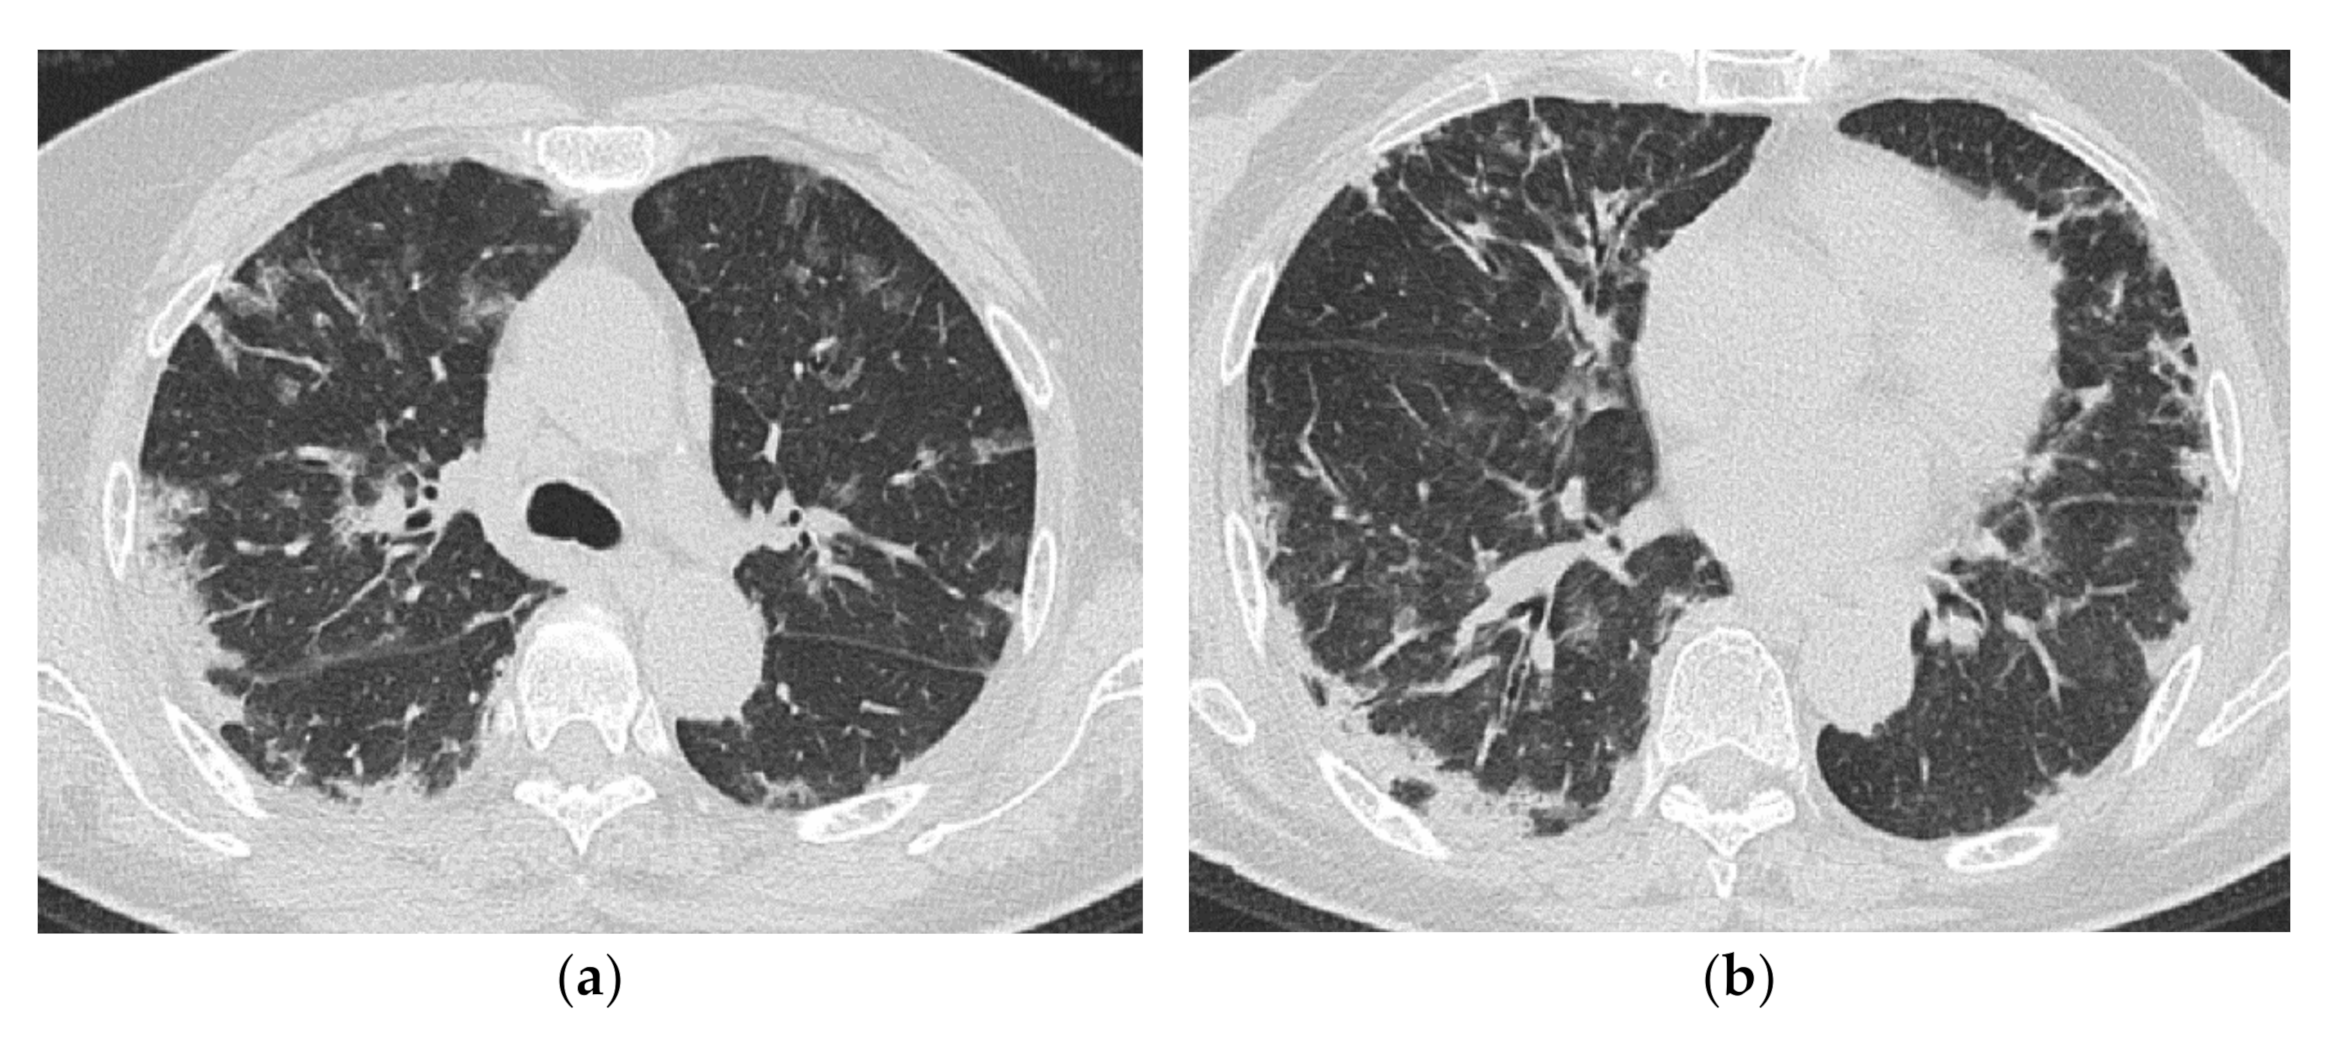

5. Clinical Pearls from HRCT Findings